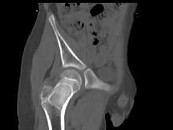

- 单项选择题男,13岁, 右髋部疼痛不适,无红肿, 结合所提供的图像,最可能的诊断是 ( )

E、骨纤维结构不良